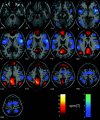

Recent neuroimaging studies have lead to the proposal that rest is characterized by an organized, baseline level of activity, a default mode of brain function that is suspended during specific goal-oriented mental activity. Previous studies have shown that the primary function subserved by the default mode is that of an introspectively oriented, self-referential mode of mental activity. The default mode of brain function hypothesis is readdressed from the perspective of the presence of low-frequency blood oxygenation level-dependent (BOLD) functional magnetic resonance imaging (fMRI) signal changes (0.012-0.1 Hz) in the resting brain. The results show that the brain during rest is not tonically active in a single mode of brain function. Rather, the findings presented here suggest that the brain recurrently toggles between an introspectively oriented mode (default mode) and a state-of-mind that tentatively might be interpreted as an extrospectively oriented mode that involves a readiness and alertness to changes in the external and internal environment.